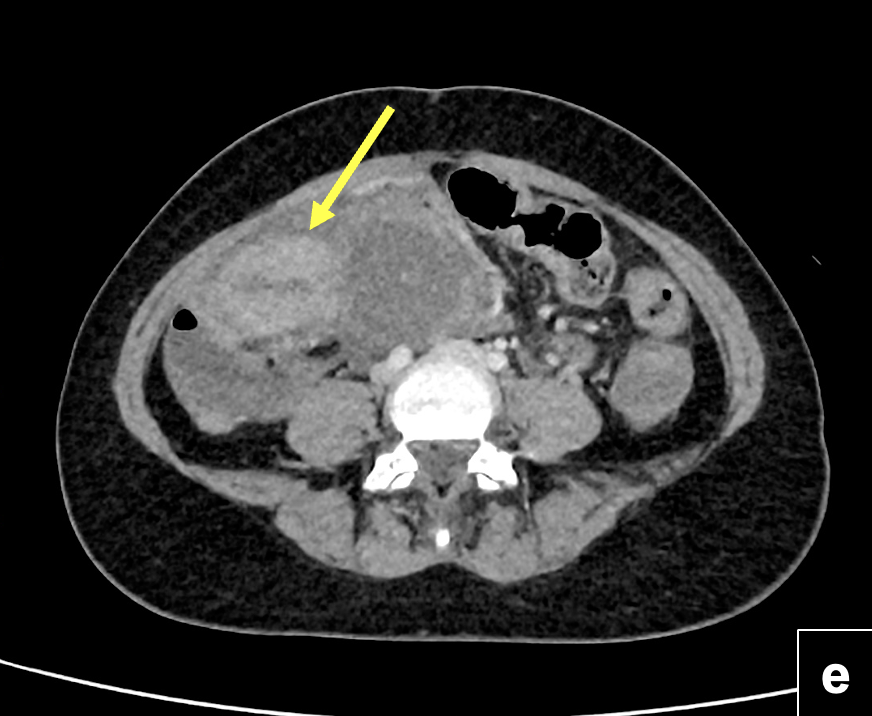

TC de abdomen y pelvis: (d) y (e): estudio coronal y axial con contraste que evidencia tumor sólido de íleon distal, con extenso componente sólido – quístico que se aloja en el hemiabdomen inferior. Se observa realce heterogéneo del componente solido (flecha). También es posible visualizar leve cantidad de líquido peritoneal y mayor densidad del tejido adiposo circundante.